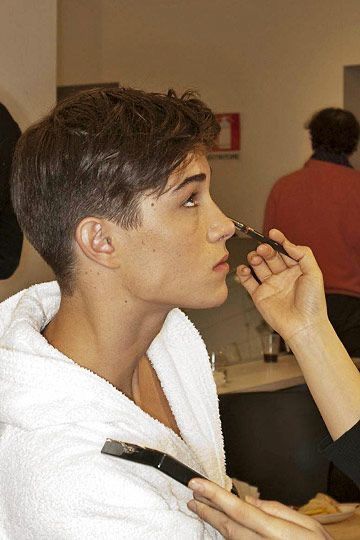

Case study #1)

Yes this isn't a true side profile but we can still compare as the orientatation is similar.

A dead giveaway is the Nasolabial angle becoming more acute - this means the nasal spine and the A point haven't moved as one and thus the relationship has changed.

Case study #1)

Yes this isn't a true side profile but we can still compare as the orientatation is similar.

A dead giveaway is the Nasolabial angle becoming more acute - this means the nasal spine and the A point haven't moved as one and thus the relationship has changed.